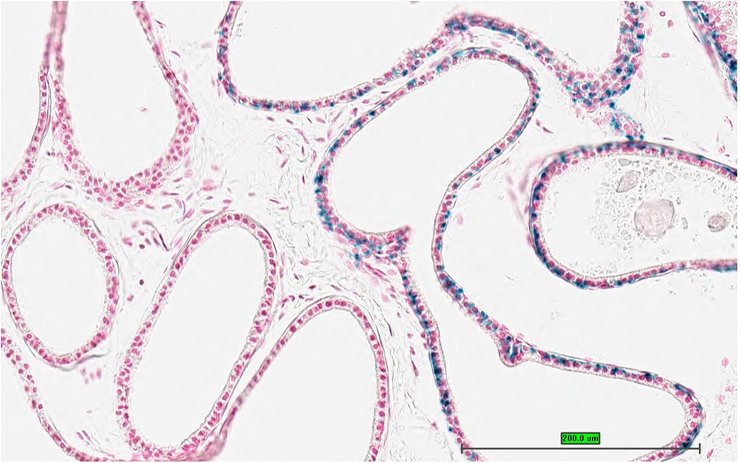

TS28: epididymis Present UC Davis_1868302

Specimen UC Davis_1868303: postnatal adult; Gabrr2tm1b(KOMP)Wtsi/Gabrr2+ (more )

Structure Level Pattern Image Note

TS28: epididymis Present UC Davis_1868303